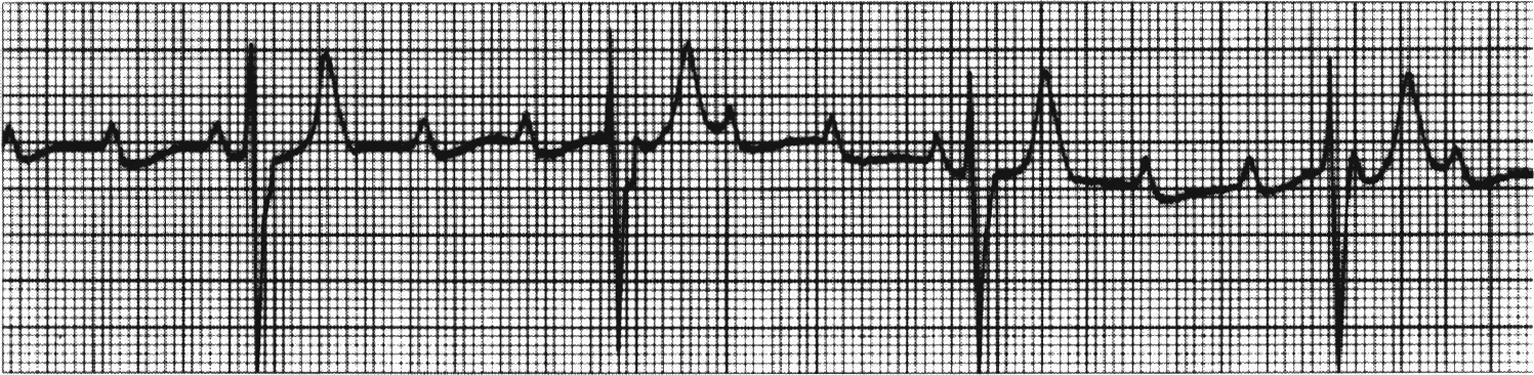

心电图显示:交界性逸搏心律、完全性房室传导阻滞,极度心动过缓

正常人心率在60-100次/分之间,心动过缓患者的基础心率一般在50次/分以下,低于40次/分将非常危险。张先生的心率这么缓慢,这是一种严重的心律失常,不仅影响患者的生活质量,心脏随时还有可能停跳导致猝死,结合检查结果,必须安装心脏起搏器。